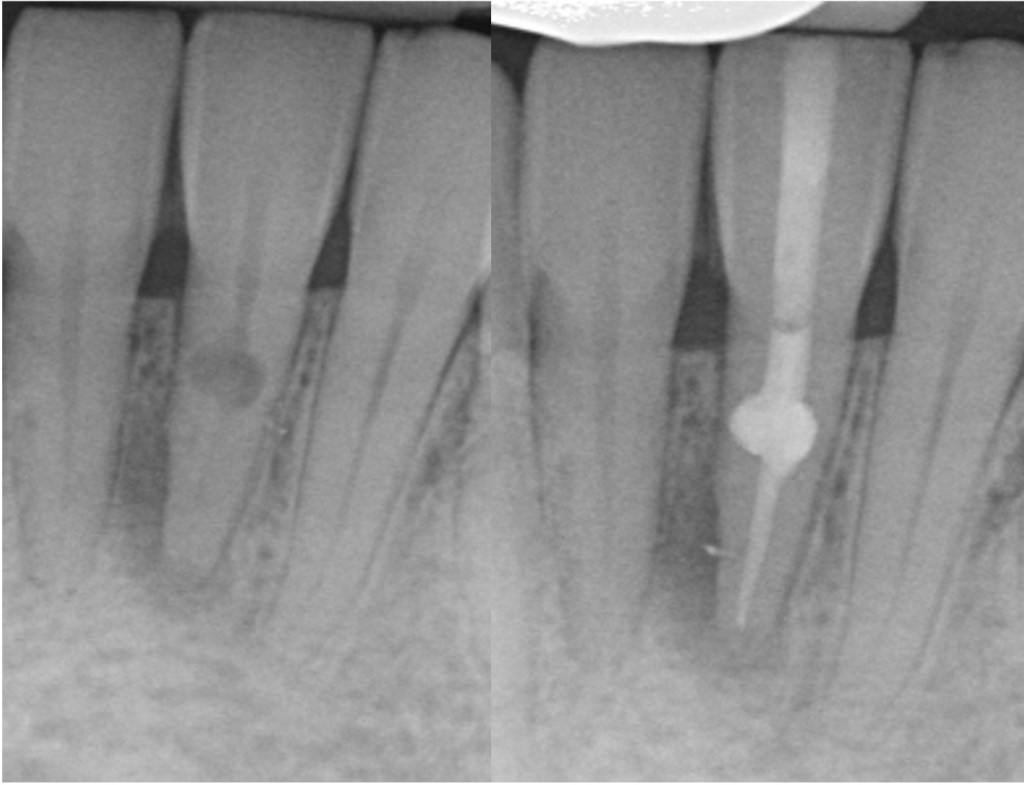

Separated instruments

Separated instruments can occur during root canal treatment. These may be able to bypassed or removed to allow completion of the root filling.